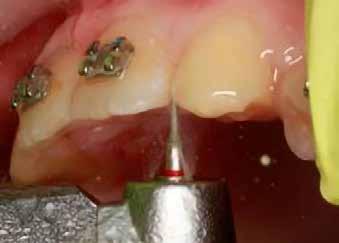

sok korrigálása, valamint az impaktálódott fog előtöréséhez szükséges hely megteremtését követően, egy merev acél ív segítségével stabilizáltuk a fogakat. Ezt követően elvégeztük a jobb felső nagymetszőfog sebészi feltárását. A fog koronáját csupán lágyrész borította, ezért nem volt szükség a csontállomány elvételére. A felszabadítás során egy 975

nm-es hullámhosszon pulzáló üzemmódban alkalmazott lézert használtunk (LaserHF standard, Hager & Werken). A teljesítménye 3 W, az aktív ciklus-idő 50%-os, a vezetőszál átmérője pedig 0,4 mm volt (2. ábra). A lézert 150 másodpercen keresztül alkalmaztuk. A fogat borító lágyrészek eltávolítását követően egy láncos brekettet rögzítettünk a metszőfog bukkális felszínére. A műtétet követően nem tapasztaltunk vérzést, nem alakult ki oedema, valamint a páciens sem számolt be fájdalom vagy bármely egyéb kellemetlenség fennállásáról. A felszabadítást követően a páciens minden hónapban háromszor jelent meg a felszabadított területre ránövő lágyrészek és az íny lézeres eltávolítása céljából. A beavatkozások során ugyanazt a lézer készüléket használtuk, mint amivel a felszabadítást végeztük. Közvetlenül a felszabadítást követően megkezdtük a fog finom extrudálását a láncos breketthez kötött füzérgumi segítségével.

Szemfog becsiszolás

A szemfog elcsiszolásához piros gyémántfúró javasolt, finom szemcsézettséggel, 27-76 µm (okkluzálisan lekerekített – Rodentica, speciális hegyű 806314466514031, Komet 8833), gyorsítóval (max 160 000 fordulat/perc) megfelelő hűtés mellett, legalább 50 ml/perc. Ezt követi a felület kidolgozása és polírozása sárga gyémántcsiszolóval, extra finom szemcsézettséggel, 10-36 µm (Rodentica 806314466504031) és narancssárga Sof-Lex korongokkal (finom alumínium-oxid szemcsék 3-40 µm, extra finom, narancssárga-sárga, alumínium-oxid kristályok mérete 1,7 µm) könyökdarabban (25000 fordulat/perc) megfelelő hűtés mellett min. 50 ml/perc (2. a-d. ábra).

A szemfog megfelelő inklinációjának eléréséhez az oldalsó metsző helyén a palatinális felszínt is el kell csiszolni. Ennek a felületnek nem szabad interferenciát okoznia a harapásban, és lehetővé kell tennie a megfelelő metszőfog-vezetést [14]. A formázás előtt meg kell vizsgálni a szemfog vesztibulo-orális pozícióját. Lapos vesztibuláris felszínnel rendelkező szemfog esetén szükség lehet egy elsőrendű hajlításra a középső metsző és szemfog között (főleg, ha a szemfogon egy oldalsó metsző bracket van, melyben a beépített in-out érték magasabb) annak érdekében, hogy elérjük a megfelelő vesztibulo-orális pozíciót a fognyak szintjén, és elkerüljük a palatinális elcsiszolást (3. a-b ábra), [39].

Kisőrlő becsiszolása

Ha a szemfog helyére mezializált kisőrlő intrúziójára nincs is szükség, a palatinális csücsök akkor is akadályozhatja a harapást és a szemfogvezetést [44]. Ezekben az esetekben elcsiszoljuk a palatinális csücsköt (8. a-b ábra) piros gyémántcsiszolóval (finom, 27-76 µm, éli formázóval – Rodentica speciális tűhegy 806314466514031, Komet 8833 vagy GD – lándzsa Rodentica 806314257514020, Komet 0640) gyorsítóban (max 160 000 fordulat/perc) vízhűtés mellett, min. 50 ml/perc [39]. Extra finom sárga gyémántcsiszolóval polírozunk, 10-36 µm szemcsézettséggel (sárga éli csiszoló Rodentica speciális tűhegyű 806314466504031, GD – sárga lándzsa alakú Rodentica 806314257504020) és narancs Sof-Lex korongokkal (3M finom, narancssárga-alumínium-oxid kristály 3-40 µm nagysággal, extra finom, narancssárga-sárga, 1-7 µm alumínium-oxid kristályokkal) könyökdarabban (25 000 fordulat/perc) legalább 50 ml/ min. hűtéssel. Az elcsiszolást több lépésben végezzük, és ezt helyi fluoridalkalmazás követheti.